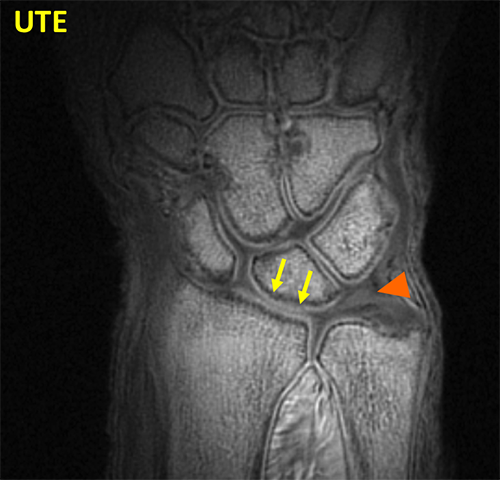

Wrist UTE

UTE sequence of the wrist shows bright signal in the deep and calcified layer of cartilage (arrow) and in the triangular fibrocartilage (arrowhead) (TFC).